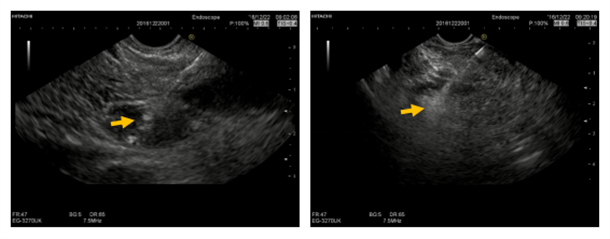

2016.12.22.行FNA穿刺活检与无水乙醇消融术,将穿刺针准确刺入。病变内留取样本送检,超声监控下注射无水乙醇1.6ml。